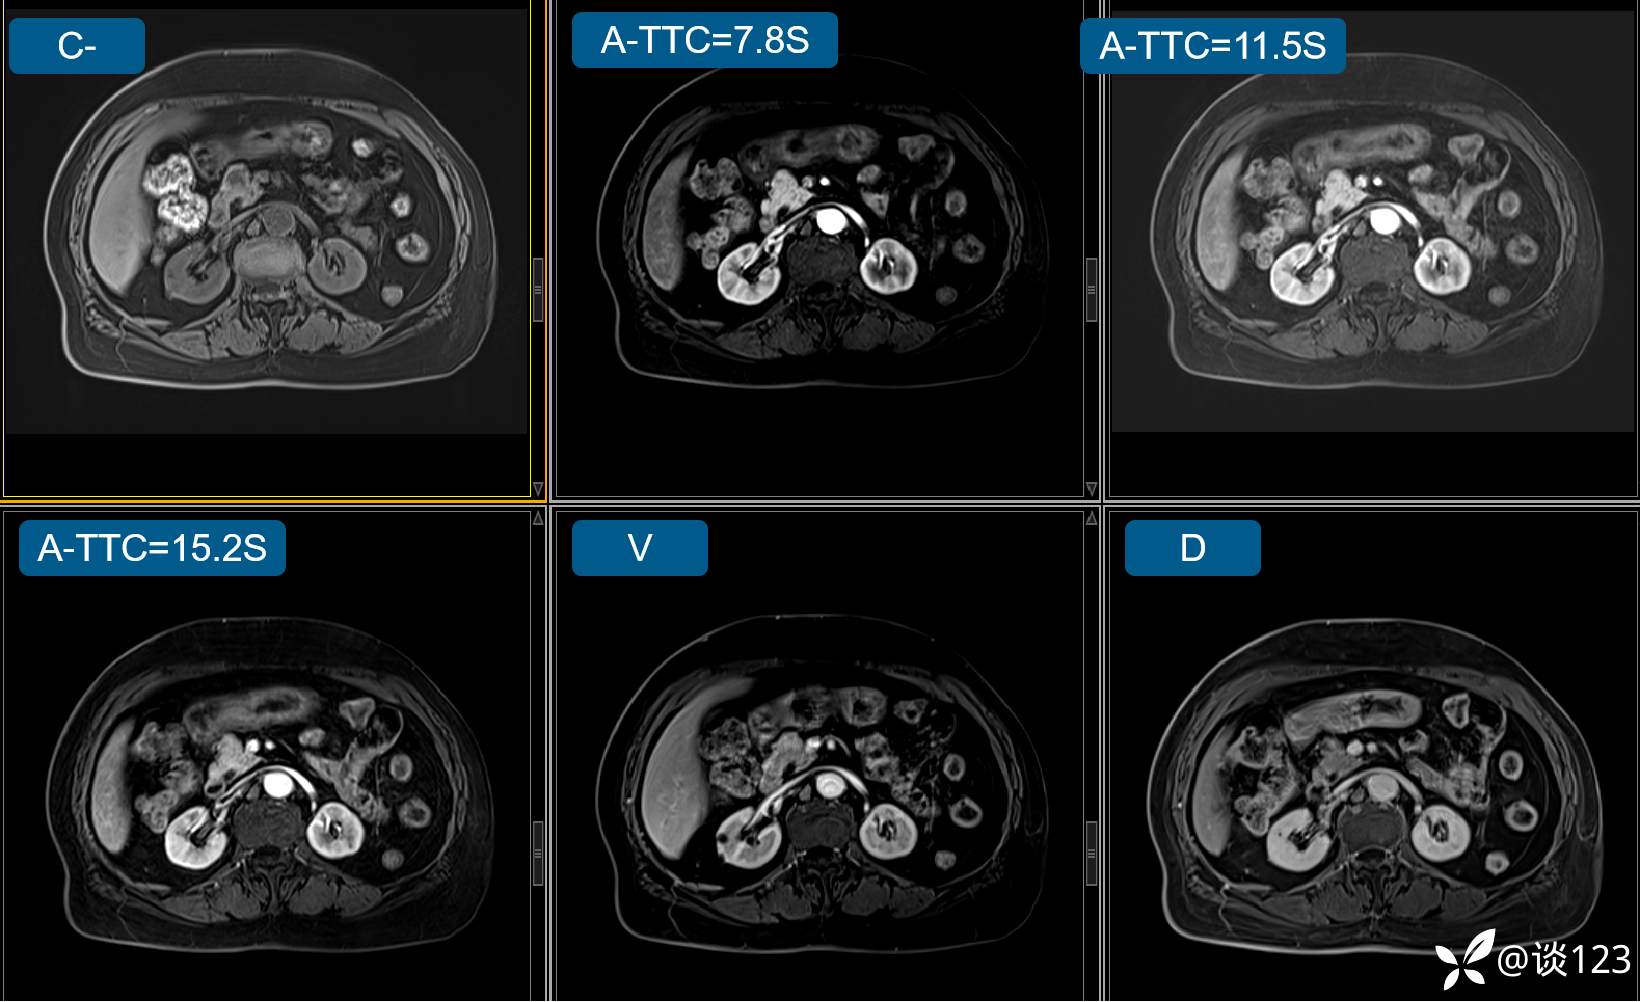

先做的CT:

C-

A

V

D

多期增强